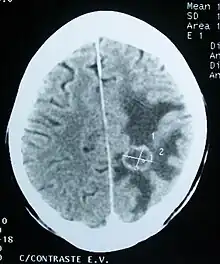

Imaging

Medical imaging plays a central role in the diagnosis of brain tumors. Early imaging methods – invasive and sometimes dangerous – such as pneumoencephalography and cerebral angiography have been abandoned in favor of non-invasive, high-resolution techniques, especially magnetic resonance imaging (MRI) and computed tomography (CT) scans,[38] though MRI is typically the reference standard used.[41] Neoplasms will often show as differently colored masses (also referred to as processes) in CT or MRI results.

- Benign brain tumors often show up as hypodense (darker than brain tissue) mass lesions on CT scans. On MRI, they appear either hypodense or isointense (same intensity as brain tissue) on T1-weighted scans, or hyperintense (brighter than brain tissue) on T2-weighted MRI, although the appearance is variable.

- Contrast agent uptake, sometimes in characteristic patterns, can be demonstrated on either CT or MRI scans in most malignant primary and metastatic brain tumors.

- Pressure areas where the brain tissue has been compressed by a tumor also appear hyperintense on T2-weighted scans and might indicate the presence of a diffuse neoplasm due to an unclear outline. Swelling around the tumor known as peritumoral edema can also show a similar result. This is because these tumors disrupt the normal functioning of the BBB and lead to an increase in its permeability.

More recently, advancements have been made to increase the utility of MRI in providing physiological data that can help to inform diagnosis and prognosis. MRI itself is sufficient in identifying the brain tumor’s location and morphology, but other types of MRI may be used on top of that, such as MRA, MRS, pMRI, fMRI, and DWI. These imaging techniques help doctors and surgeons to diagnose the type of tumor, to plan for surgery, and to assess treatment and radiation/chemotherapy.